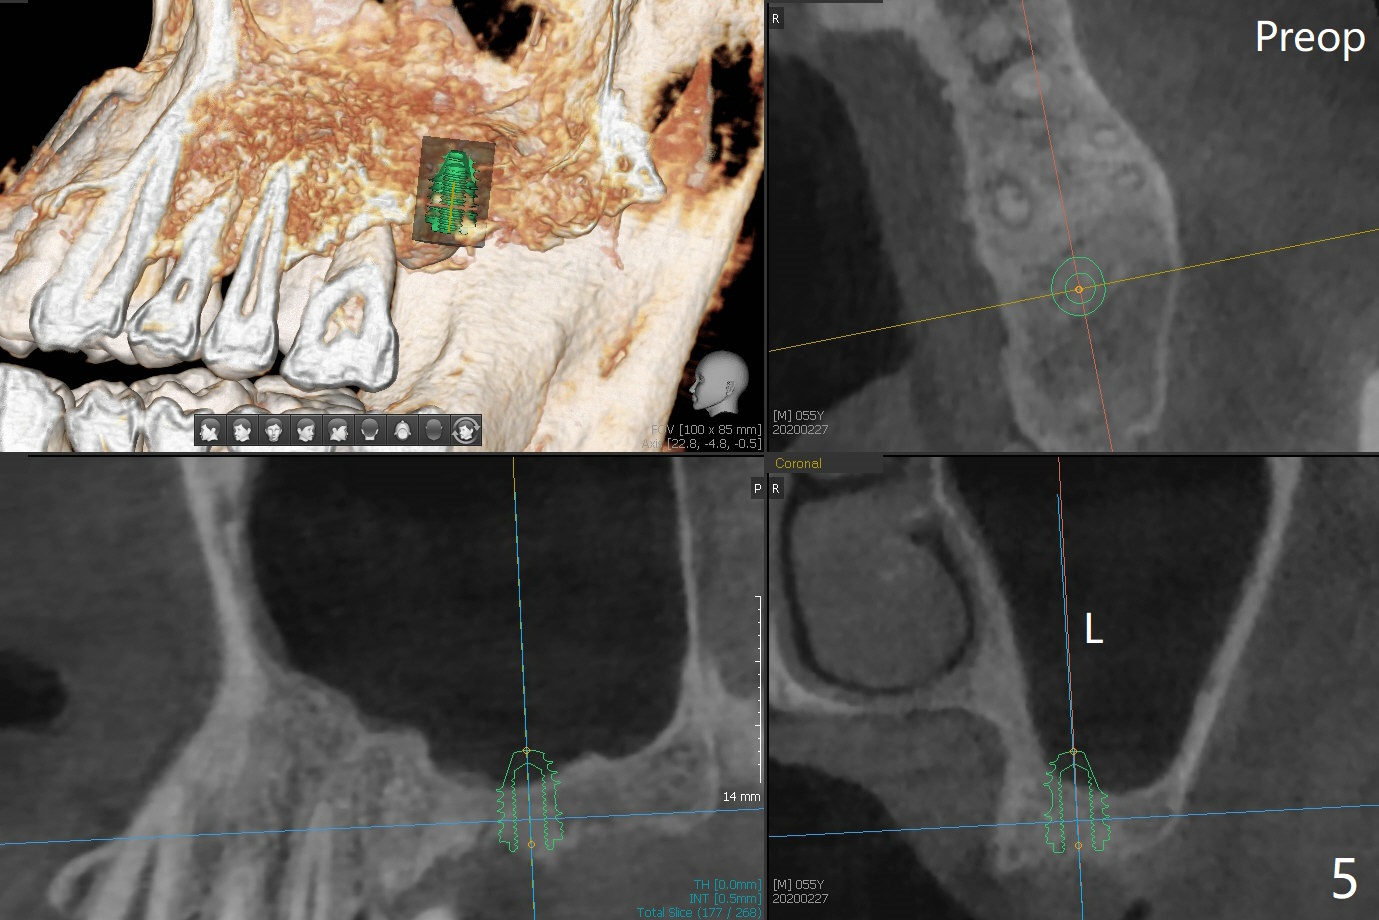

左上7完成初步钻洞,园钻头无法插入导板金属圈,用2.2毫米钻头钻深2毫米,窦膜似乎完整,在没有骨粉情况下,使用4x10毫米报废植体做上颌窦提升(图一),可能一下提升太多,窦膜破了,塞入两小块胶原膜,注入NovaBone

Putty (in

cartridge),植入短小植体(4.5x7毫米,原定(5x8.5毫米)图二),由于稳定性好,使用5.5毫米profile钻头后,放置5.5x4毫米愈合基台(图三)。术后病人没有什么上颌窦不适和分泌物。估计Novo

Bone在上颌窦里凝固了。其实左侧上颌窦粘膜术前增厚(图四,五:L),人工骨仿佛弥撒在上颌窦膜中(图六)。术后一周病人没有任何鼻窦症状。术后4.5月旋转愈合基台时,病人感到疼痛,终止取模(图七),两个月后复诊,做progressive loading。术后5.5月旋转愈合基台时,植体一起出来,但是上颌窦膜没有破,放置大一号植体(报废)扭力不够(图八),再大一号扭力可以(图九),放置愈合帽。由于邻牙长(图九:双箭头),牙周敷料逗留三周不掉(图十:P)。撤除后,伤口愈合正常。The